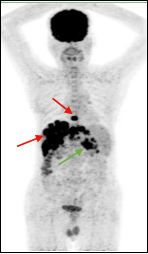

淋巴瘤治疗前后变化: 弥漫性大B细胞淋巴瘤化疗3程后,腹腔及腹膜后多发肿大淋巴结明显缩小,糖代谢明显减低。

(上两图为:治疗前,下两图为:治疗后)

淋巴瘤治疗前后变化:弥漫性大B细胞淋巴瘤化疗3程后,腹腔机腹膜后多发肿大淋巴结明显缩小,糖代谢明显减低。根据Deauville标准 5PS评分为2分。